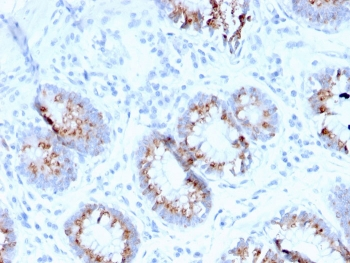

IHC staining of FFPE human colon carcinoma with MerTK antibody (clone TPKR-1). HIER: boil tissue sections in pH9 10mM Tris with 1mM EDTA for 10-20 min and allow to cool before testing.